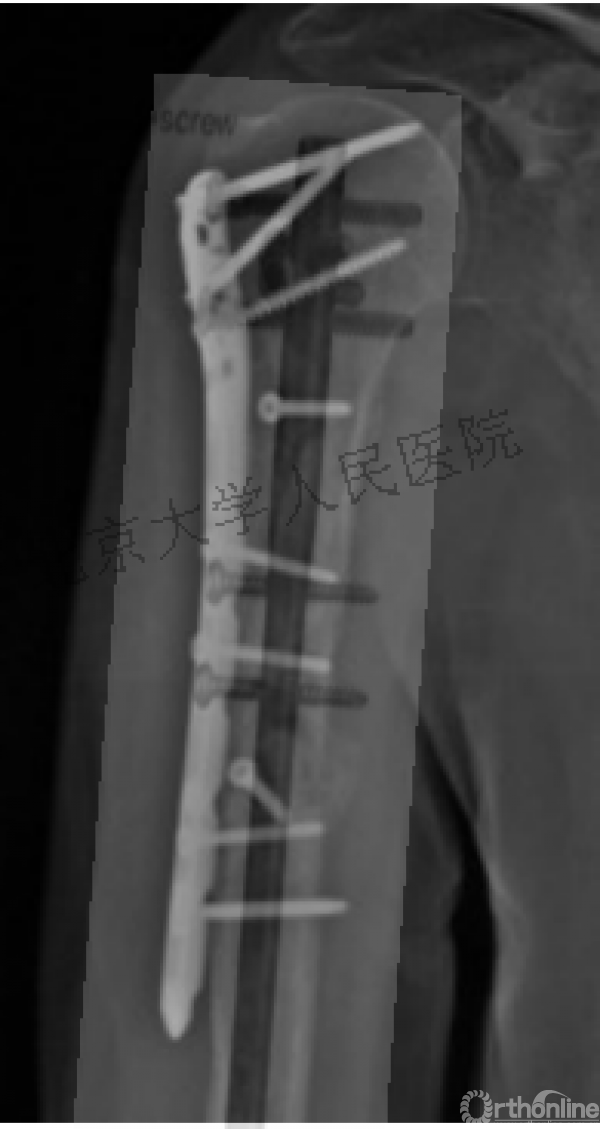

病例

可否有更好的进钉和复位的更好帮助办法?

进钉更完美——我们的帮助

术中片